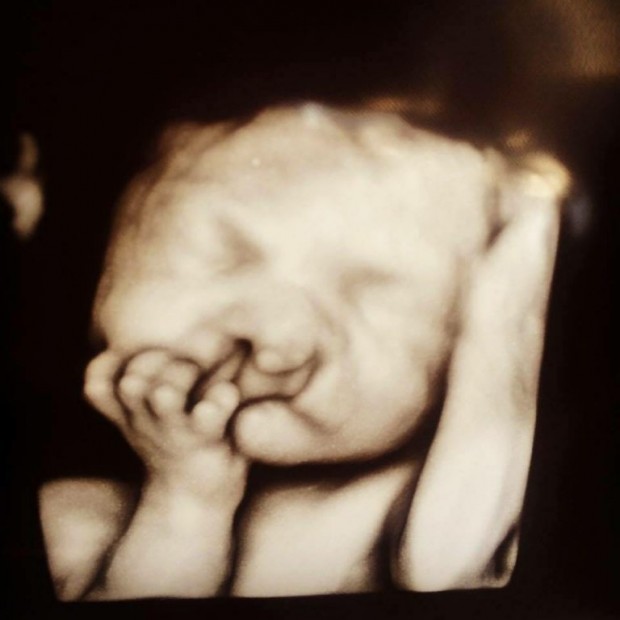

Bebek sahibi olmak insanın hayatını değiştiriyor. Hissettiğiniz sevgiyi kelimelerle ifade edemiyorsunuz. Evladınız için en iyisini yapmaya çalışıyorsunuz.Ultrasona bakıldığında Brody’nin dudaklarının tam olarak gelişmediği ve damağının yarık olduğu görüldü. Brody’nin dudağı ile burnu arasında büyük boşluk vardı."DEVAM ETMEK GÖRSELE TIKLAYARAK İLERLEYİNİZ..

Brody’nni ebeveynleri ultrasonu görünce üzüldüler.Doktorlar, Brody gibi dünyada sadece 9 çocuk olduğunu söylediler.Chris Eidam, Omaha News’e “Bize çocuğu aldırıp aldırmamak istediğimizi sordular” dedi. Sara ve Chris, bebeği aldırma fikrini bir an olsun akıllarından geçirmediler.Anne, Today.com’a “Bebeğiniz nasıl görünürse görünsün onunla gurur duymalısınız. Bebeğimizin önceki ve sonraki fotoğraflarını sosyal medyada paylaşarak bu hastalık hakkında insanların bilinçlenmesini sağlamak istedik” dedi."DEVAM ETMEK GÖRSELE TIKLAYARAK İLERLEYİNİZ..